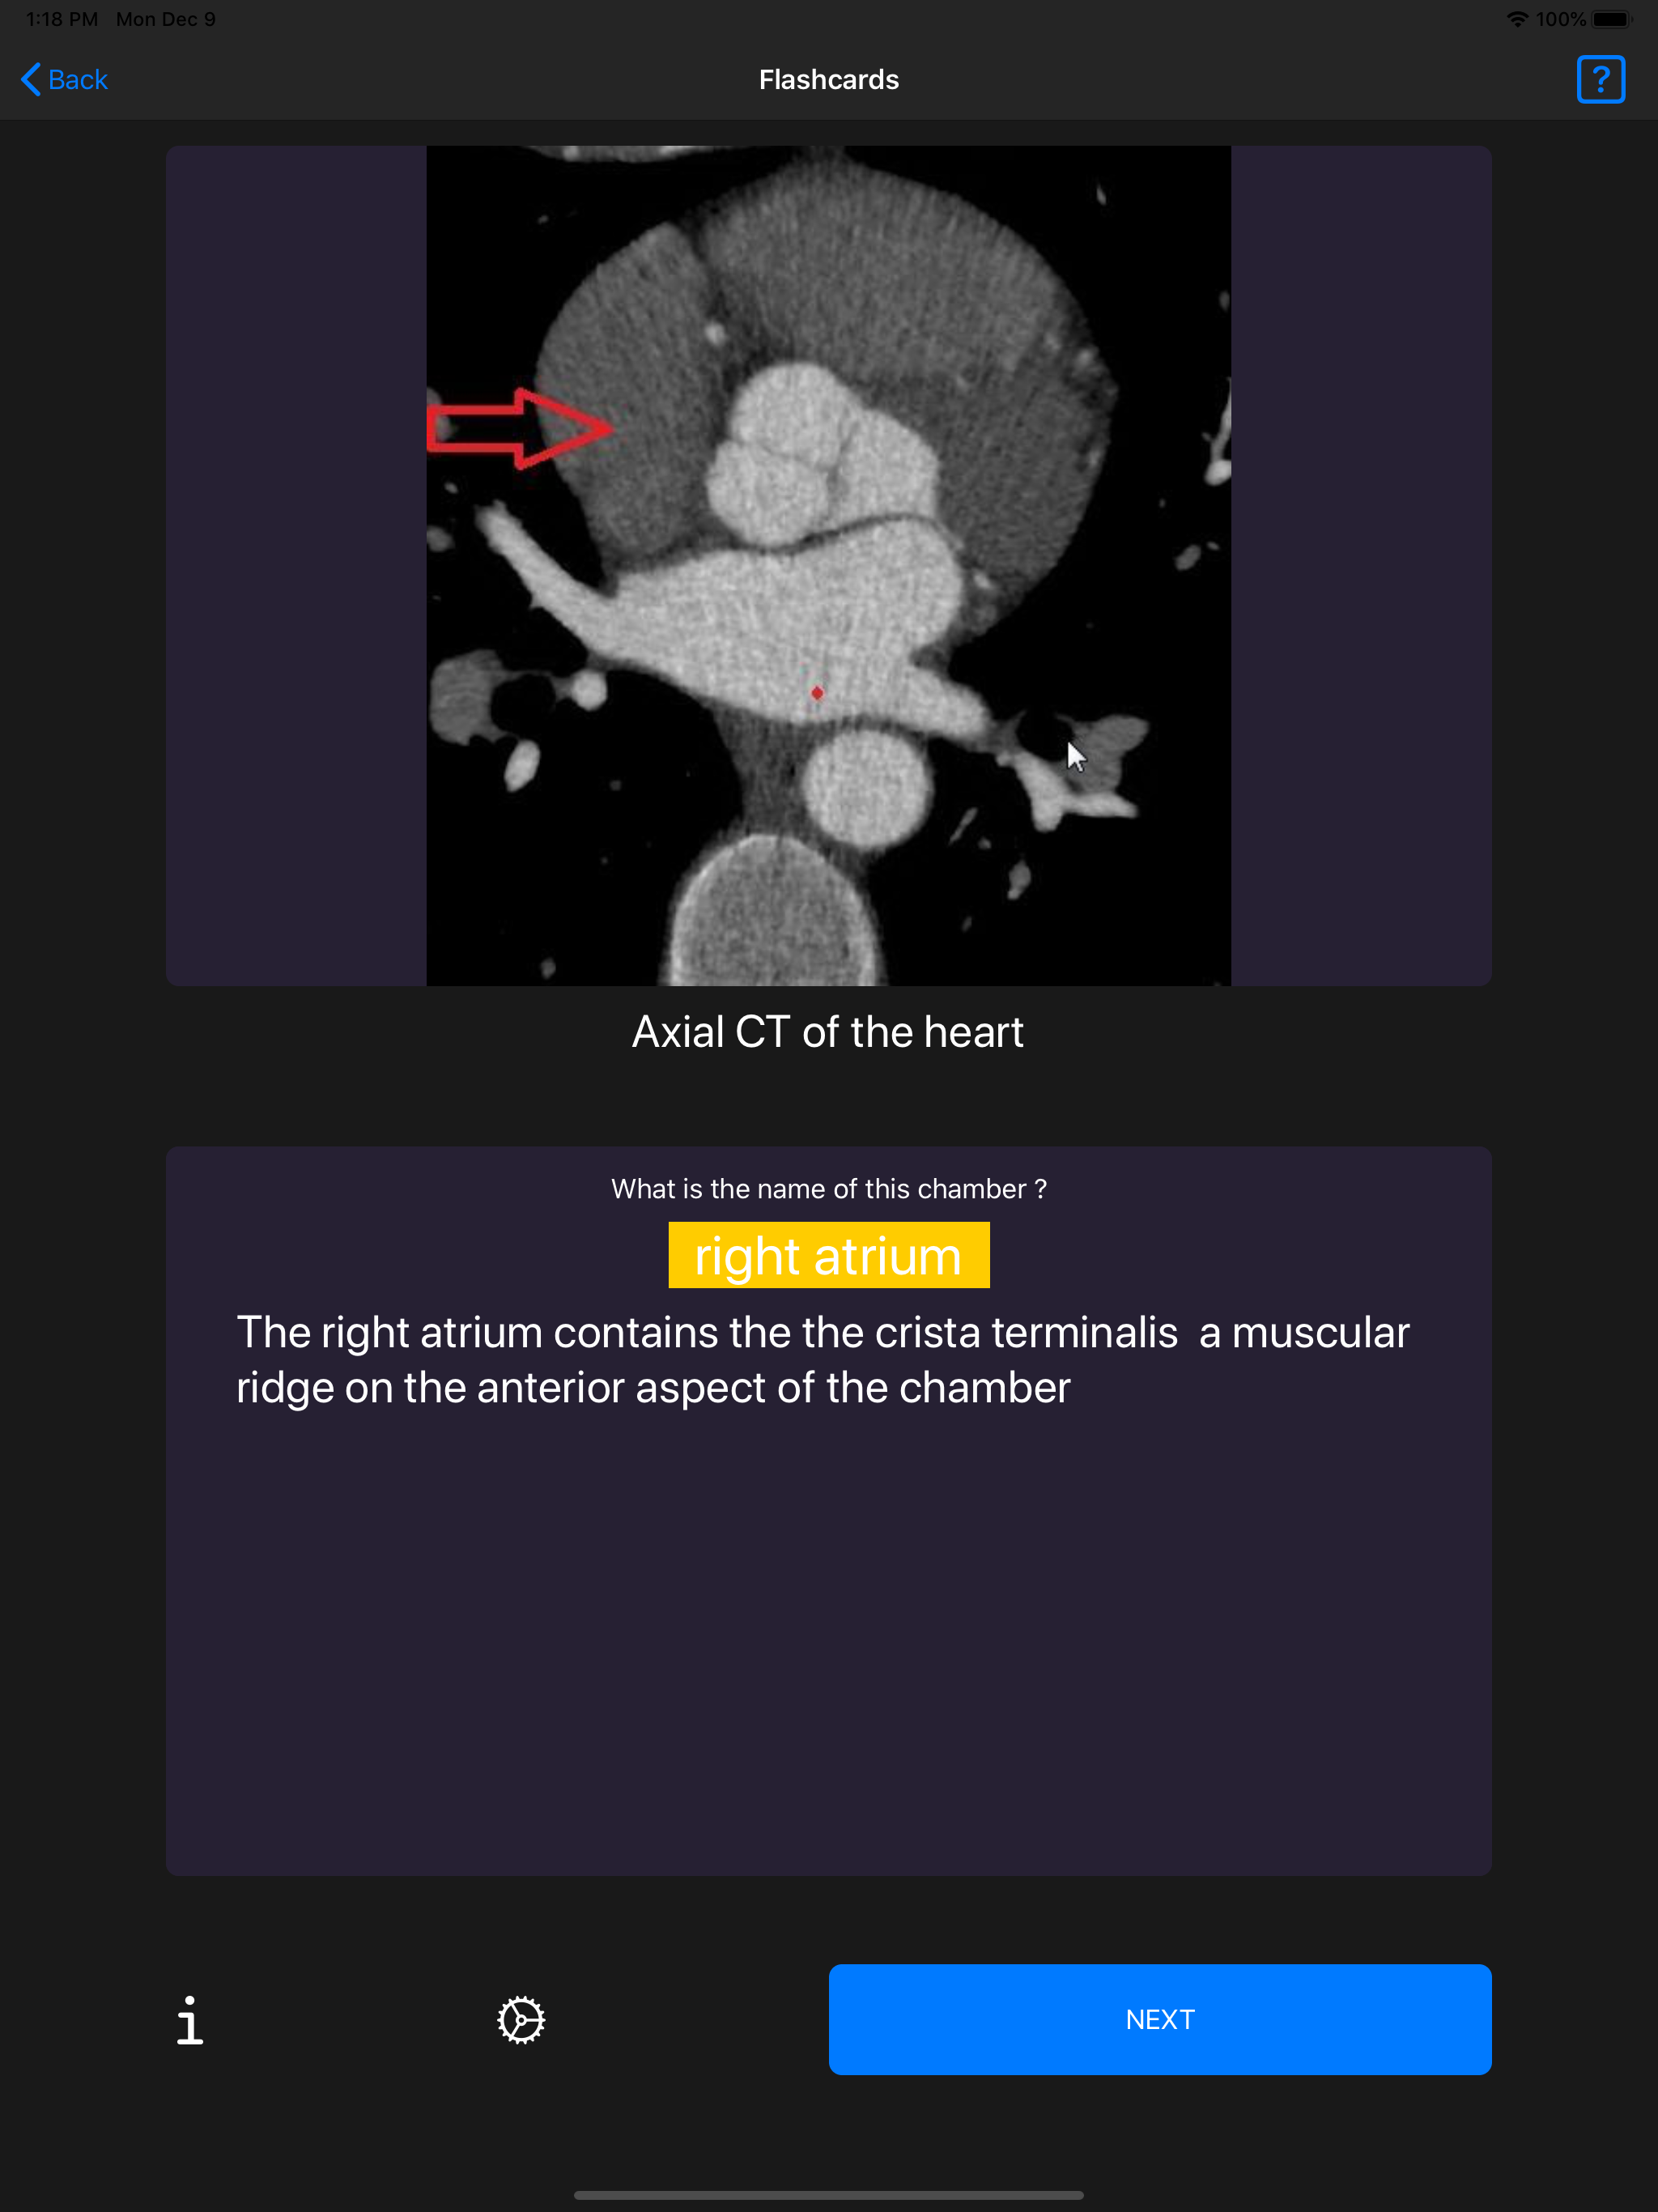

Over 1,000 flashcards containing labelled images . The answers are hidden and you can check the correct answer as soon as you are ready. Key learning points are shown with each flashcard shown. There are three difficulty levels that you can alter whenever you wish. The flashcards are updated and added to constantly. This application relies on an internet connection. There is no sign-up required and is free for use as much as you wish. All images are original and labelled. This application is produced by MCQS.com , an exam preparation site that offers quiz questions that will help you prepare for your part 1 and part 2 Radiology FRCR exams. Any queries , corrections, to MCQS.com.